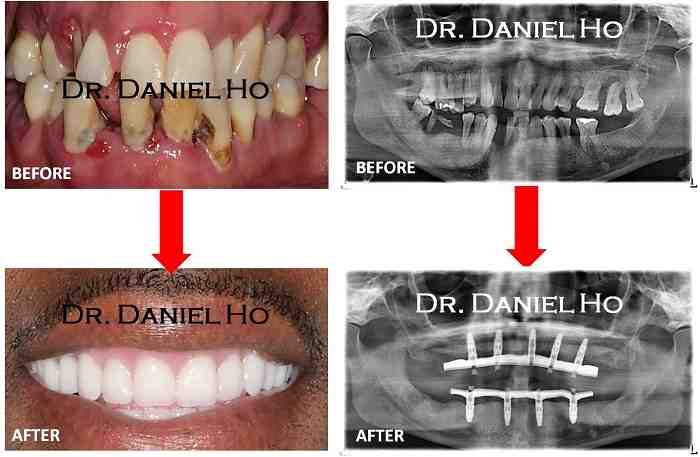

The “teeth in the sun” events usually refer to a full arch tooth replacement, in which all diseased teeth are removed, implanted implants, and a temporary version of your teeth implanted “all in one visit. To see also : How Long Do Mini Dental Implants Last. Several months later, after the healing has taken place, the last teeth will be replaced.

Dental implants usually provide the right answer. An increasing number of dentists offer them one-day dental sets using state-of-the-art implants and, quickly, refining what is implanted. These systems rely on implants placed in such a way that they cannot move within recovery.